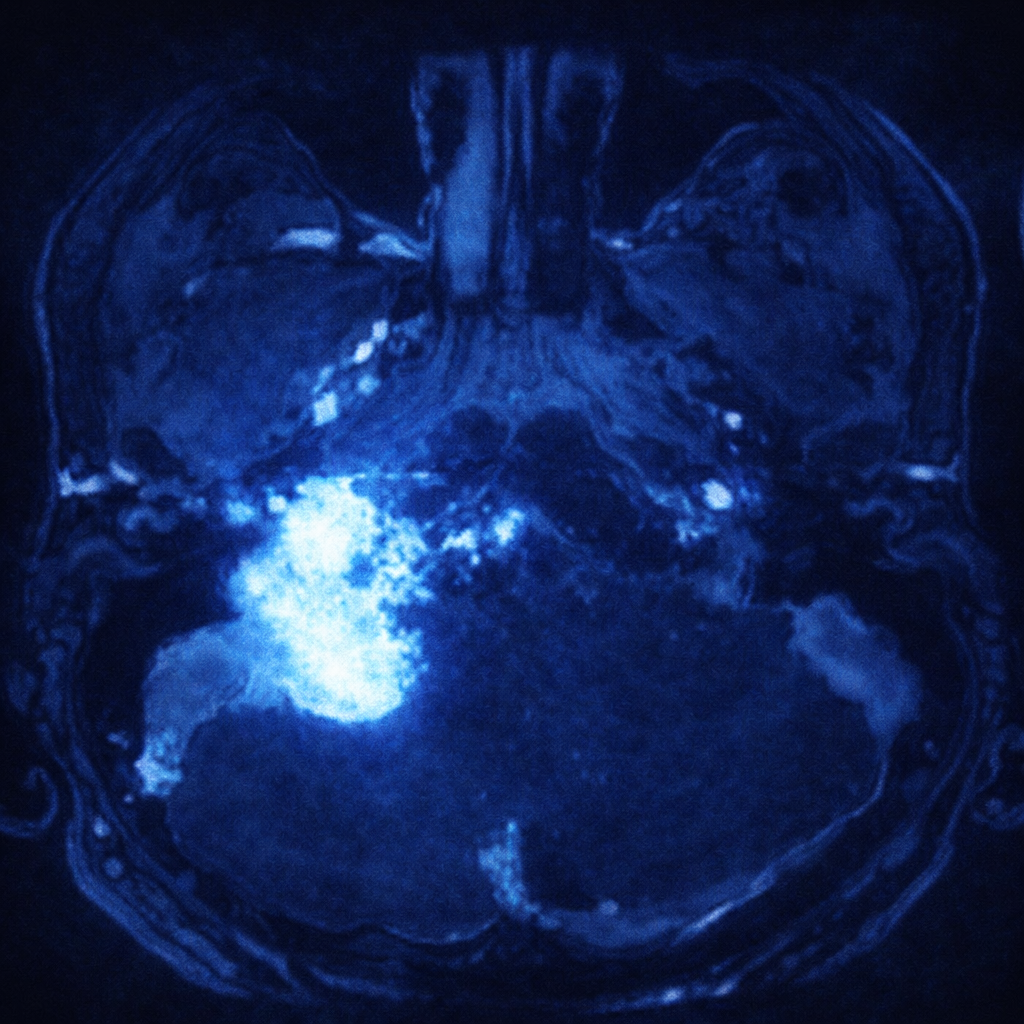

La resonancia magnética es el estudio apropiado para estudiar un glomus yugular. Generalmente, estos tumores captan medio de contraste de manera regular, aunque pueden tener grandes componentes quísticos.

En las tomografías, es característico encontrar una tumoración que amplía y erosiona el foramen yugular y el hueso temporal.